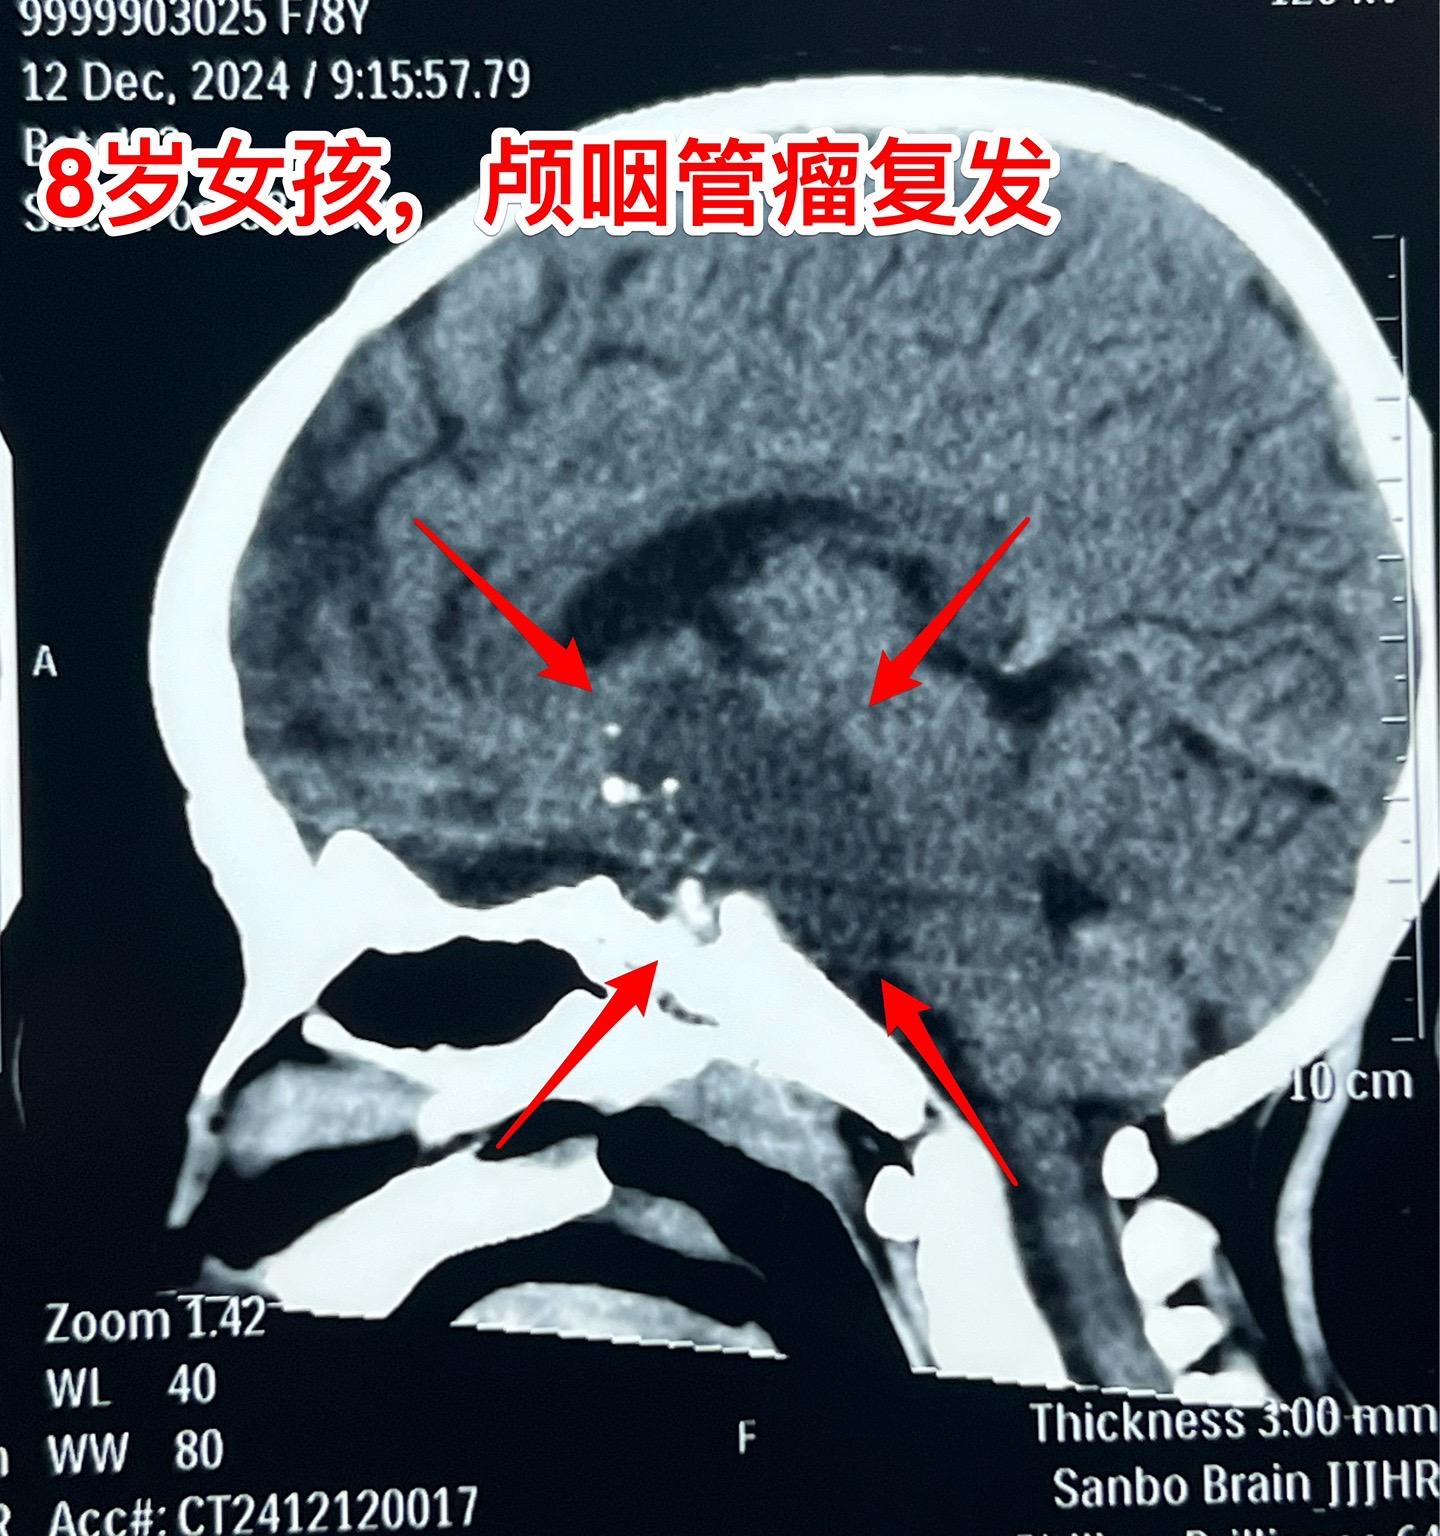

八岁女孩,终于完成了颅咽管瘤切除手术。8岁承德市围场县女孩子,颅咽管瘤手术后两年复发了,视眼视力很差。10月份曾经在我科住院,准备做手术。我在10月31日发的视频中跳舞的就是这个女孩子。当时因为经济原因和医保方面的障碍,未能作手术,回家筹集资金。 12月11日小女孩再次来住院。经过四十多天的等待,小女孩的病情更加恶化了,她的双眼视力更差了,几乎看不见了。磁共振和CT可以显示肿瘤体积巨大。 12月13日作了开颅手术,手术过程顺利。手术后小女孩很快就清醒了,昨晚就转回了普通病